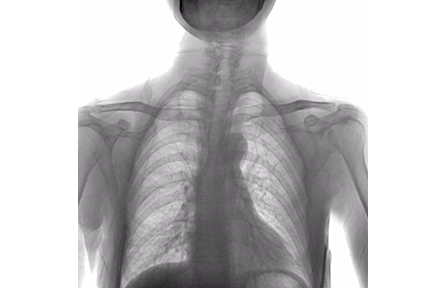

PerfoX 7500 为各种检查提供一体化成像解决方案。配备动态平板探测器,可提供高对比度的静态和动态成像。系统支持影像拼接功能,提供全旋转和下肢的全景图像

一体化成像解决方案,可满足广泛的临床应用

l 数字化摄影

满足人体各个部位拍摄需要